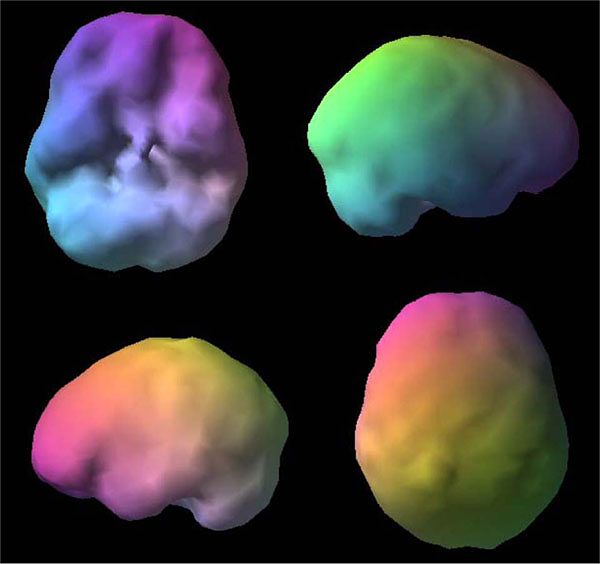

[Picture]

Healthy SPECT image of the brain: Smooth surfaces with soft indentation that indicates separate regions of the brain.